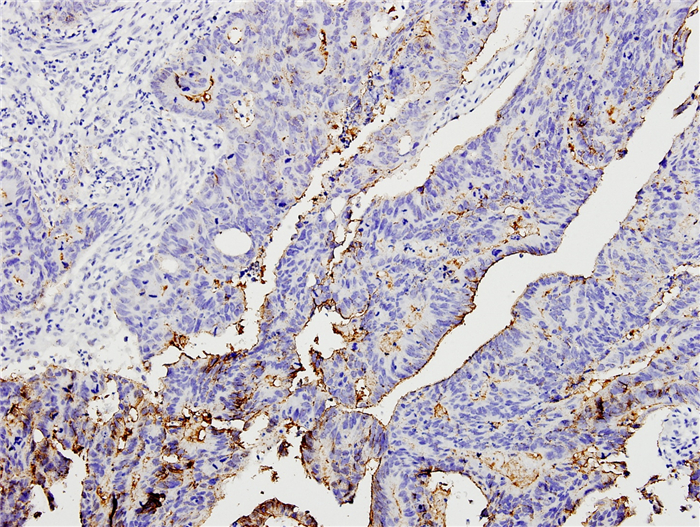

2 结果 2.1 Claudin-3蛋白在结直肠癌组织及癌旁正常组织中的表达情况与比较免疫组化检测结果显示,claudin-3蛋白主要分布在细胞膜上,呈颗粒状或团块分布,在细胞质和细胞核亦可有表达,呈浅黄色至棕褐色不等的颗粒,基底部及腺腔内分泌物也偶尔可见一定程度的染色(图 1~3)。癌组claudin-3蛋白的阳性表达率为92.5%,高于癌旁正常组的59.09%,差异有统计学意义(χ2=10.105,P=0.003,P < 0.05);癌组claudin-3蛋白的强阳性表达率为40%,癌旁正常组为27.27%,两组差异无统计学意义(χ2=1.004,P=0.316,P>0.05,表 1)。有13例癌组织和癌旁正常组织来自同一病例,这13例病例的癌组织和癌旁正常组织中claudin-3表达平均评分分别为4.538和3.269,配对T检验分析显示,癌组织claudin-3的表达强于自身癌旁正常组织,差异有统计学意义(P=0.019,P < 0.05,图 4)。以上结果提示claudin-3蛋白在癌组织中的表达显著强于癌旁正常组织,claudin-3蛋白的异常表达可能可以作为结直肠癌的诊断指标。

图 3 结直肠癌低分化组织中claudin-3强阳性(++)表达 Figure 3 strongly positive (++) expression in poorly differentiated colorectal carcinoma (SP, ×200). |